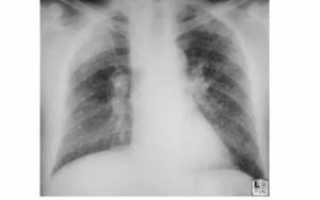

Основным методом выявления нарушений в тканях легких является флюорография. Ее необходимо проводить ежегодно, а категориям людей, входящим в группу риска по легочным заболеваниям – два раза в год. Если имеется подозрение на наличие плевральных спаек, то пациента отправляют на рентген легких.

Прямым признаком, указывающим на наличие спайки, являются тени, которые видны на рентгене. При этом она не меняется во время выдоха и вдоха больного. Также будет снижена прозрачность легочного поля. Возможны деформации грудной клетки и диафрагмы. Кроме того, диафрагма может быть ограничена в подвижности. Чаще всего такие спайки располагаются в нижней части легкого.

Для обнаружения легочных заболеваний в первую очередь используется флюорография. Эту процедуру необходимо проводить ежегодно, в основном она направлена на выявление ранней стадии туберкулеза. Однако опытный рентгенолог может выявить на снимке образовавшиеся плевральные спайки, которые выглядят тенями. Причем форма их не меняется в зависимости от вдоха и выдоха.

При необходимости дополнительно назначается рентген. Как правило, спайки располагаются в нижней части легкого. При этом будет более темная картинка, а также может быть частичная деформация грудной клетки и диафрагмы.